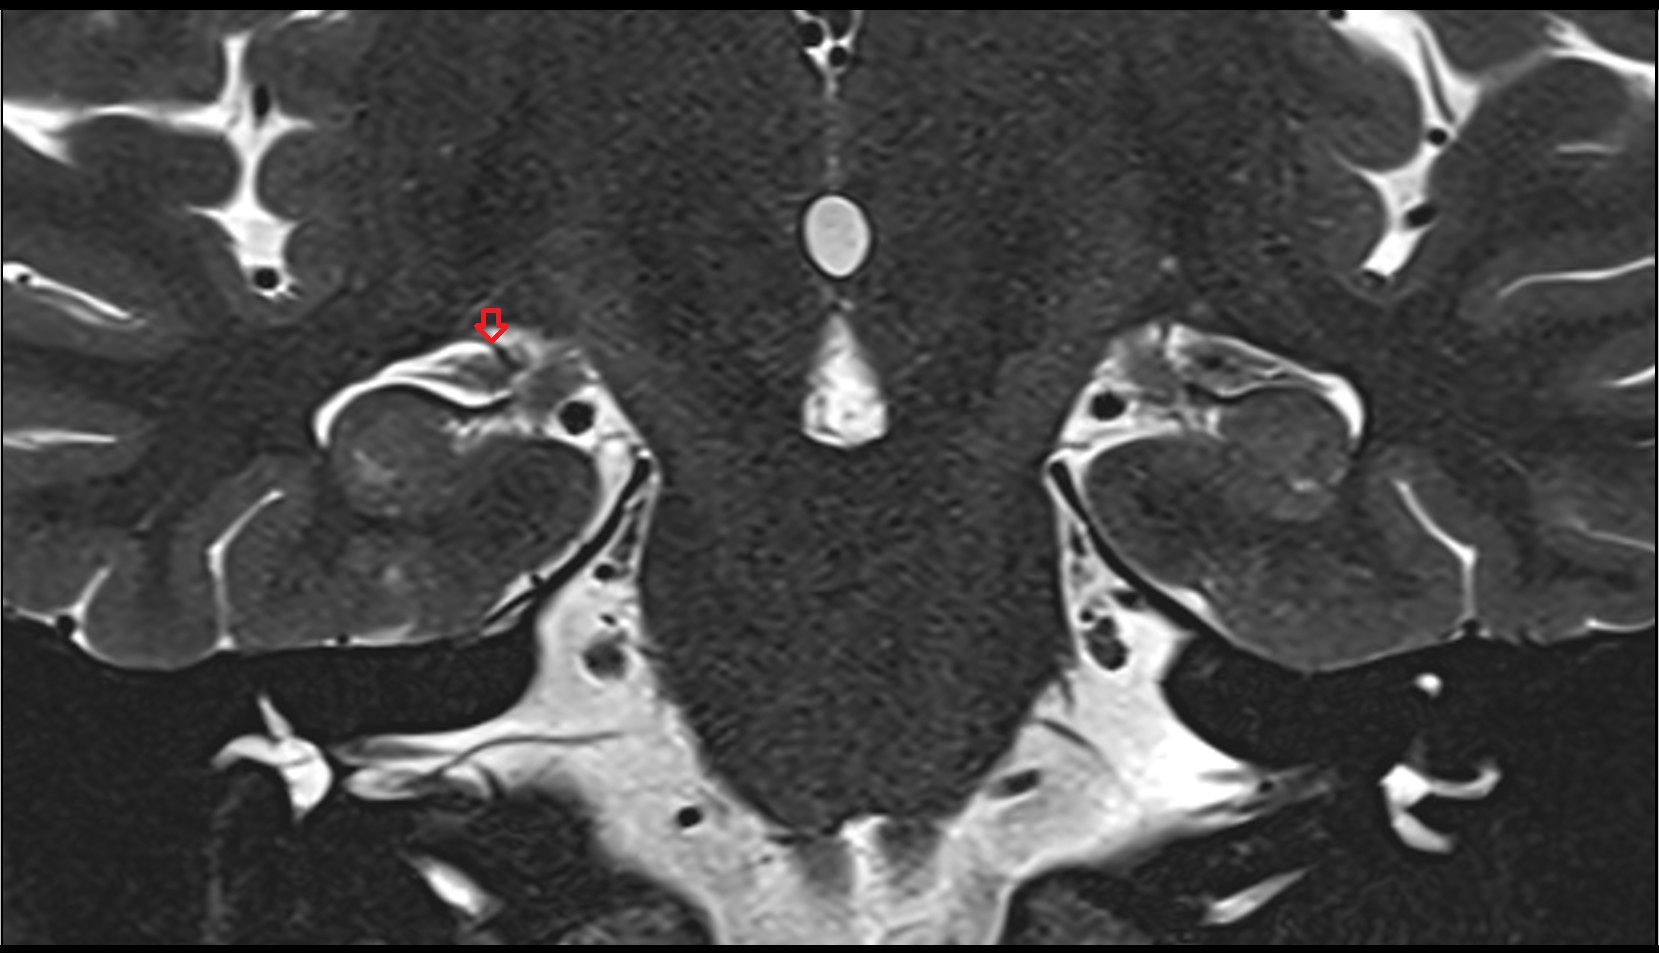

- Peripheral zone of prostate

- Anterior Fibromuscular Stroma of prostate

- Central zone of prostate

- Transitional zone of prostate